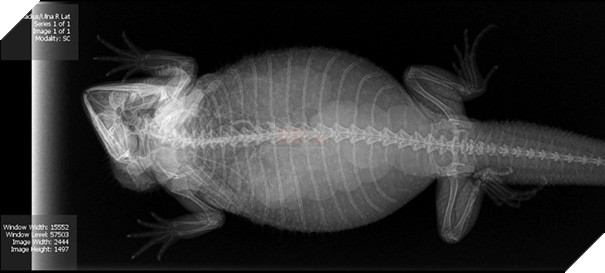

Khi rùa mang thai, những quả trứng rùa nhỏ trong bụng rùa mẹ trông như thế này đây!